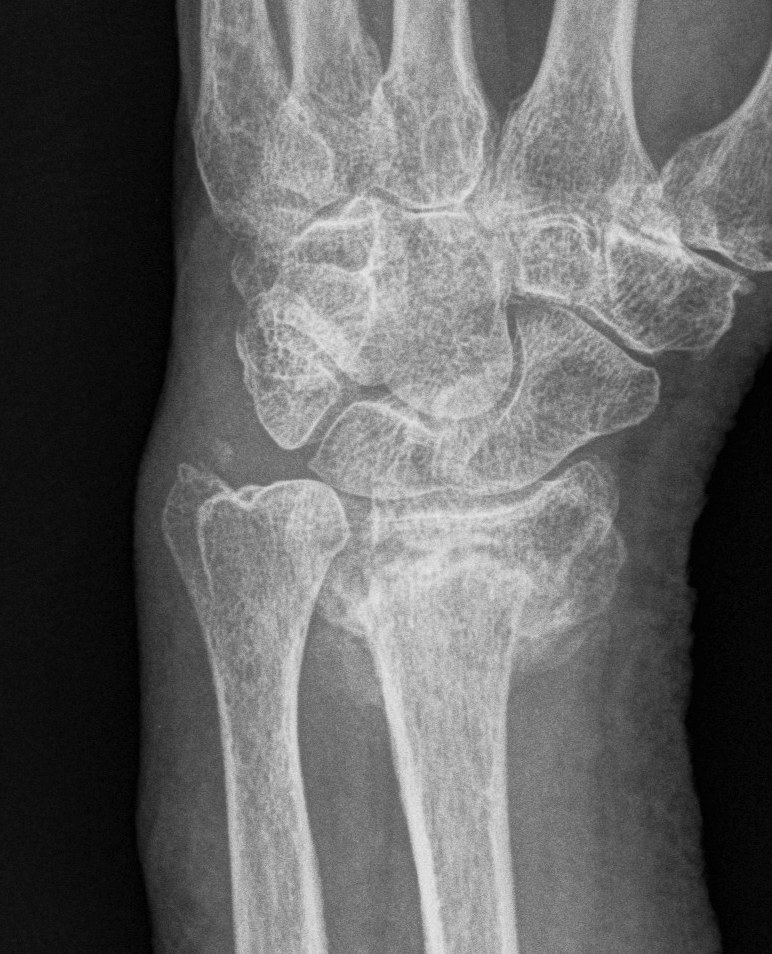

Xray

Bilateral xrays

PA film in neutral

- wrist neutral

- elbow & shoulder at 90°

malunion

Radial shortening Radial inclination Positive ulna variance

Dorsal tilt > 15 degrees Volar tilt > 10 degrees Articular step > 3 mm